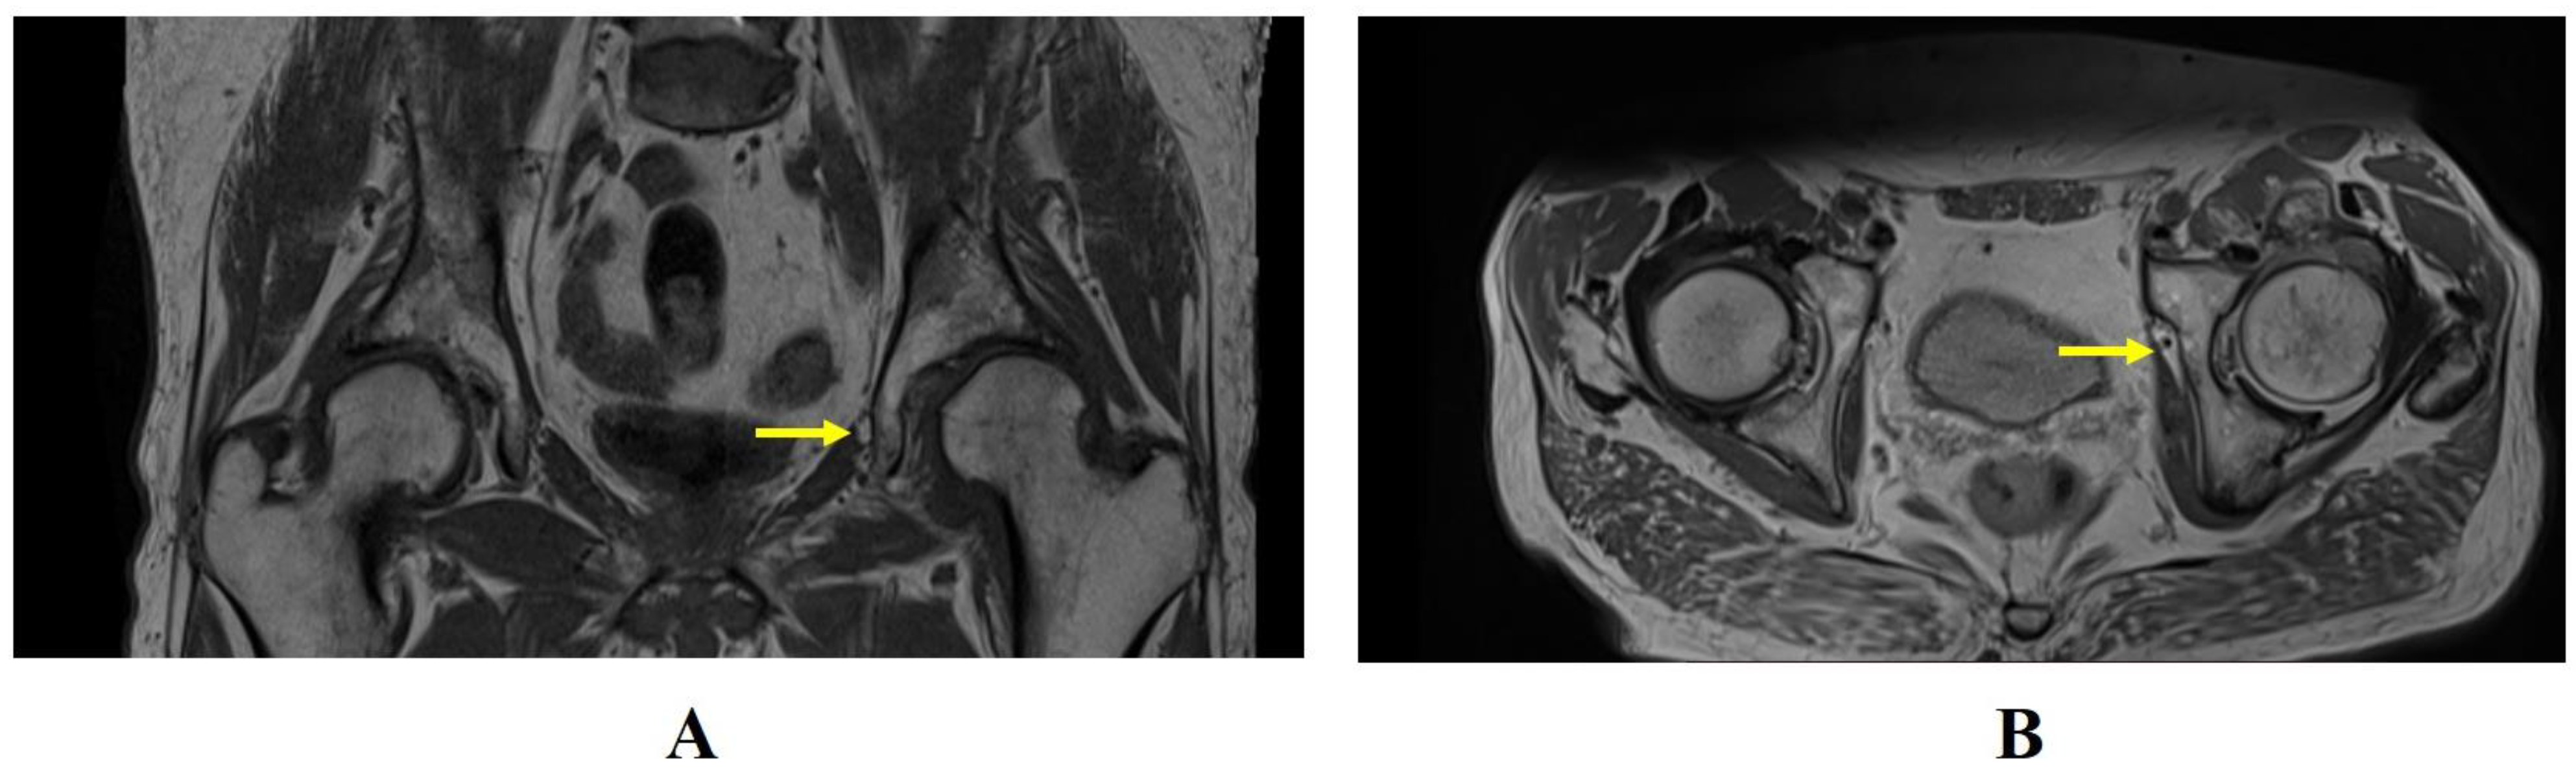

| Obturator hernia | Coronal and axial T1- and PD-weighted sequences | Protrusion of fat through the foramen between the pectineus and obturator externus muscles. Very important evaluation of the comparison for symmetry with the contralateral canal. |